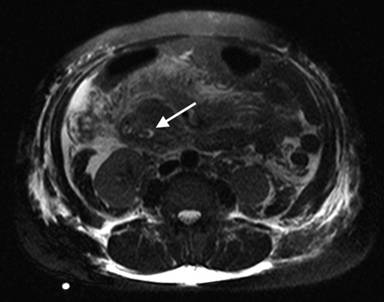

Our patient is a72-year-old woman who initially presented to an outside hospital in January 2011 with severe epigastric abdominal pain and near syncopal episode. Initial diagnostic tests revealed elevated amylase, lipase and transaminase levels. An abdominal computed tomography (CT) scan showed a diffusely edematous pancreas with peripancreatic inflammation. She was treated conservatively with bowel rest and appropriate fluid resuscitation. Once stable, she underwent magnetic retrograde cholangiopancreatography (MRCP), which indicated an intraluminal filling defect in the conjoined portion of the common bile duct and pancreatic duct near the ampulla suspicious for stone, clot or tumor (Figures 1 and 2), in addition to the marked pancreatic edema and peripancreatic inflammation (Figure 3). The patient then underwent endoscopic retrograde cholangiopancreatography (ERCP), which confirmed a lesion in the ampulla of Vater. This lesion was biopsied and thereby only partially resected. Additionally, a pancreatic stone was discovered and removed. The patient received biliary sphincterotomy and stent placement. The final pathology of the biopsy specimen revealed duodenal papillary adenoma with high-grade dysplasia. The patient convalesced from this acute episode and was discharged with planned follow-up to discuss the treatment strategy for the ampullary lesion.

Figure 2. Axial MRCP (T2 HASTE sequence, thin slice) image demonstrating intraluminal filling defect due to ampullary lesion (white arrow). |